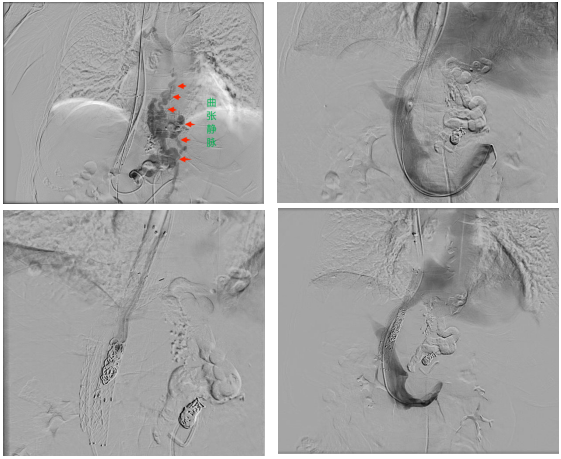

手术中,在兄弟科室的全力配合下,介入团队精准测量发现何女士门静脉压力梯度高达26mmHg,证实原通道分流量严重不足。随后,医务人员经肝右静脉成功穿刺门静脉右支,在栓塞严重曲张的静脉后,建立了一条全新的8mm分流道。

术后,门静脉压力梯度骤降至7mmHg。为了避免过度分流加重心脏负担,介入团队又巧妙地利用球囊封堵原分流道后反复测量评估门静脉压力后使用弹簧圈封堵原分流道,最终将门静脉压力梯度控制在14mmHg的理想水平。